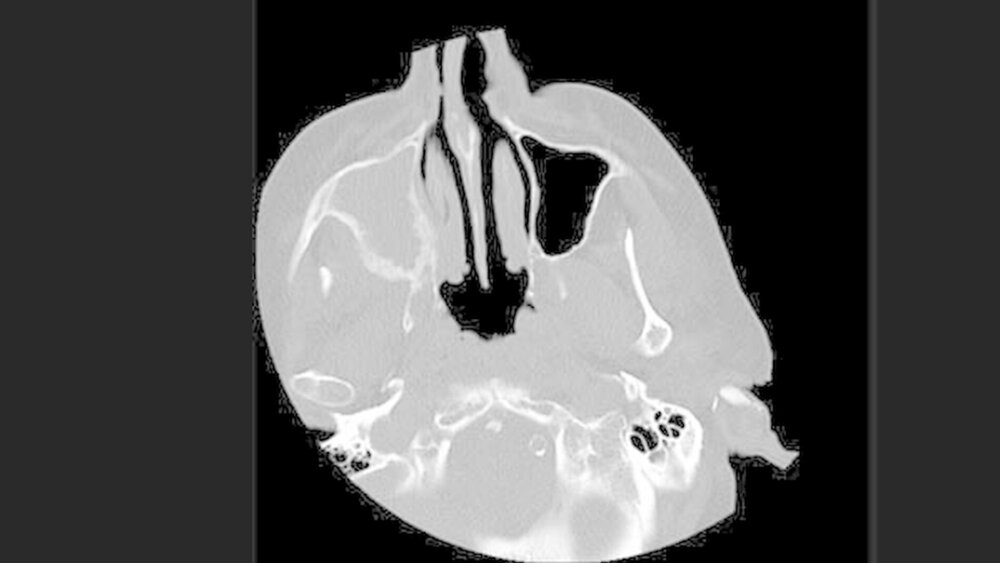

Auf dem Bild zeigte sich keine Fraktur, jedoch eine verbreiterte und unruhige Struktur der Maxilla rechtsseitig, die sich über die gesamte Wand der rechten Kieferhöhle, mit Ausnahme des Kieferhöhlendachs/Orbitabodens sowie den angrenzenden Processus pterygoideus des Os sphenoidale (Keilbein) erstreckte. Zudem war die rechte Kieferhöhle komplett verschattet (Abbildungen 1 und 2).